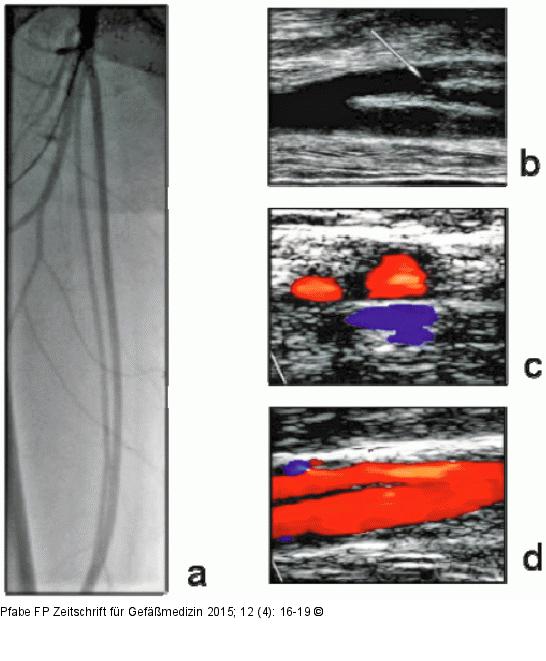

Abbildung 3a-d: Arteria femoralis superficialis Doppelung der A. femoralis superficialis rechts. (a): Angiographische Darstellung mit Visualisierung der differenten Gefäß-Kaliber; (b): sonographische Darstellung der proximalen Teilung im Längsschnitt (B-Bild); (c): Darstellung im Querschnitt des mittleren Drittels des Oberschenkels (Duplex-Mode); (d): distale Wiedervereinigung der beiden Schenkel im Längsschnitt (Duplex-Mode). |